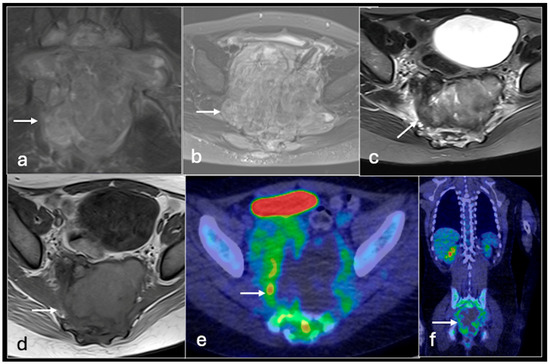

4.2. Chondrosarcoma

- Plaza de Las Heras, I.; García Cañamaque, L.; Quílez Caballero, E.; Camacho-Arias, M.; Cárdenas Soriano, M.D.P.; Martel Villagrán, J. Positron emission tomography-magnetic resonance imaging applications in pediatric musculoskeletal tumors. Quant. Imaging Med. Surg. 2024, 14, 7825–7838. [Google Scholar] [CrossRef] [PubMed] [PubMed Central]